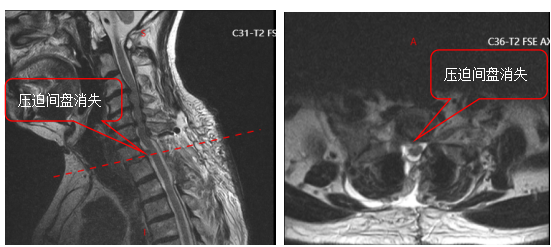

面对这一特殊情况,吴静晔主任没有急于下结论,而是为患者进行了细致全面的检查,最终精准诊断为脊髓型颈椎病。而进一步检查显示,患者存在 C3-T1 多节段狭窄,病情复杂且手术节段较多,这无疑给治疗带来了巨大挑战。

常规的治疗方案是颈后路 C3-T1 开门手术。虽能实现彻底减压,但手术损伤较大,对于 78 岁高龄的患者来说,是极大的考验。

为最大程度降低手术损伤,保障手术安全,吴静晔主任、王肖虎主任带领团队反复研讨,最终制定了更贴合患者情况的手术方案——C7-T2 节段全椎板切除减压、髓核摘除、椎弓根螺钉内固定术。

看似确定了治疗方向,真正的难题才刚刚开始。该手术区域解剖结构极其复杂,毗邻人体重要的神经、血管,堪称脊柱外科的「珠峰」。尤其是 C7-T2 椎弓根螺钉置入环节,传统手术极度依赖术中 C 臂透视,却因肩部遮挡,透视、定位极为困难,不仅手术视野受限、置钉难度陡增,螺钉还极易误入椎管,导致术中减压不充分,手术效果完全依赖主刀医生的丰富经验和精湛技术,是业内公认的「硬骨头」手术。